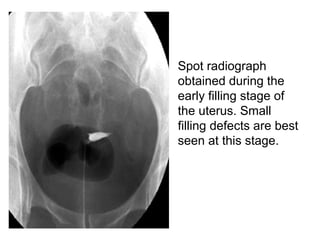

• Spot radiograph

obtained during the

early filling stage of

the uterus. Small

filling defects are best

seen at this stage.

• Spot radiograph obtainedduring the early filling stage of the uterus. Small filling defects are best seen at this stage.